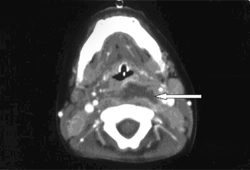

რადიოგრაფული გამოკვლევები აუცილებელია დიაგნოზის დასადასტურებლად. სასურველი კვლევის მეთოდის არჩევა დამოკიდებულია ეჭვის ხარისხზე და არსებული გამომსახველობითი კვლევების ხელმისაწვდომობაზე, ისევე, როგორც დაავადების სიმძიმეზე. მიუხედავად ამისა, კტ კვლევა მიიჩნევა ყველაზე ზუსტ დიაგნოსტიკურ მეთოდად. როგორც წესი, კონტრასტით ჩატარებული გამოკვლევისას რეტროფარინგულ ქსოვილებში ბეჭდისმაგვარი დაზიანება ვლინდება.

[Figure caption and citation for the preceding image starts]: კისრის კტ კვლევა, რომელზეც გამოსახულია ბეჭდისმაგვარი, კონტრასტით გამოკვეთილი დაზიანება.Philpott CM, Selvadurai D, Banerjee AR. პედიატრული რეტროფარინგეული აბსცესი. J Laryngol Otol 2004; 118: 919-926 [Citation ends].